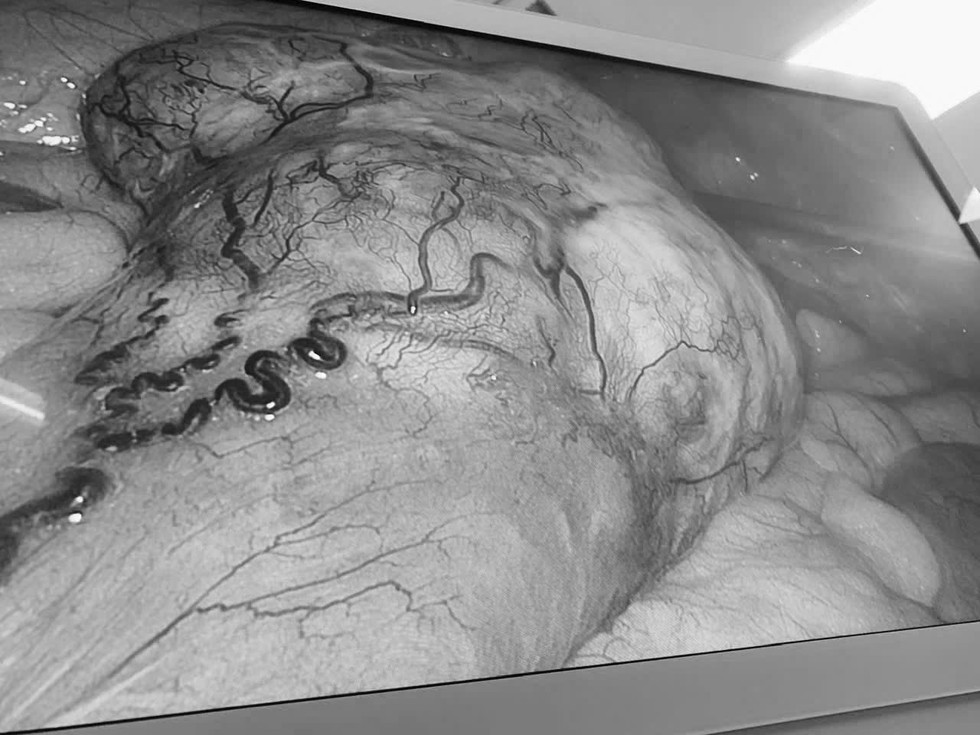

Tưởng rối loạn tiêu hóa, đi khám phát hiện khối u ruột và ung thư đại tràng- Ảnh 2.

Hình ảnh khối u được quan sát rõ qua nội soi trong quá trình phẫu thuật, giúp bác sĩ đánh giá chính xác vị trí và mức độ tổn thương

Ảnh: Nam Long